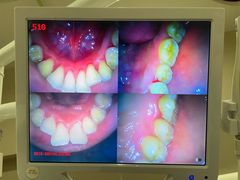

• 土豆口腔(凤凰北总店)

• -土豆口腔(凤凰北总店)